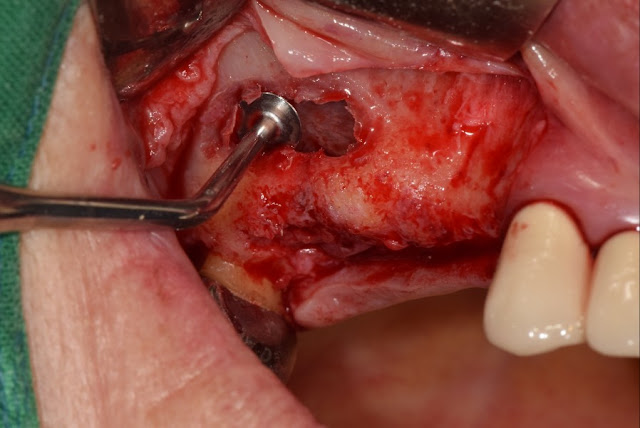

Since someone has inquired, I am showing the procedure for accessing the instrument when opening the maxillary sinus. Most of you already know this.